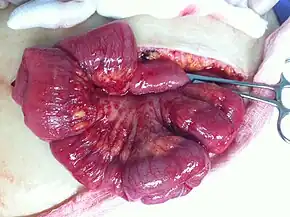

Ovarian adenocarcinoma deposit in the mesentery of the small bowel

Metastasis in ovarian cancer is very common in the abdomen and occurs via exfoliation, where cancer cells burst through the ovarian capsule and are able to move freely throughout the peritoneal cavity. Ovarian cancer metastases usually grow on the surface of organs rather than the inside; they are also common on the omentum and the peritoneal lining. Cancer cells can also travel through the lymphatic system and metastasize to lymph nodes connected to the ovaries via blood vessels; i.e. the lymph nodes along the infundibulopelvic ligament, the broad ligament, and the round ligament. The most commonly affected groups include the paraaortic, hypogastric, external iliac, obturator, and inguinal lymph nodes. Usually, ovarian cancer does not metastasize to the liver, lung, brain, or kidneys unless it is a recurrent disease; this differentiates ovarian cancer from many other forms of cancer.[29]

In advanced cancers, where complete removal is not an option, as much tumor as possible is removed in a procedure called debulking surgery. This surgery is not always successful, and is less likely to be successful in women with extensive metastases in the peritoneum, stage- IV disease, cancer in the transverse fissure of the liver, mesentery, or diaphragm, and large areas of ascites. Debulking surgery has usually only been done once[28] but a recent study has shown a longer overall survival in recurrent ovarian cancer when surgery combined with chemotherapy was performed compared to treatment with chemotherapy alone.[95] Computed tomography (abdominal CT) is often used to assess if primary debulking surgery is possible, but low certainty evidence also suggests fluorodeoxyglucose‐18 (FDG) PET/CT and MRI may be useful as an addition for assessing macroscopic incomplete debulking.[96] More complete debulking is associated with better outcomes: women with no macroscopic evidence of disease after debulking have a median survival of 39 months, as opposed to 17 months with less complete surgery.[26] By removing metastases, many cells that are resistant to chemotherapy are removed, and any clumps of cells that have died are also removed. This allows chemotherapy to better reach the remaining cancer cells, which are more likely to be fast-growing and therefore chemosensitive.[29]